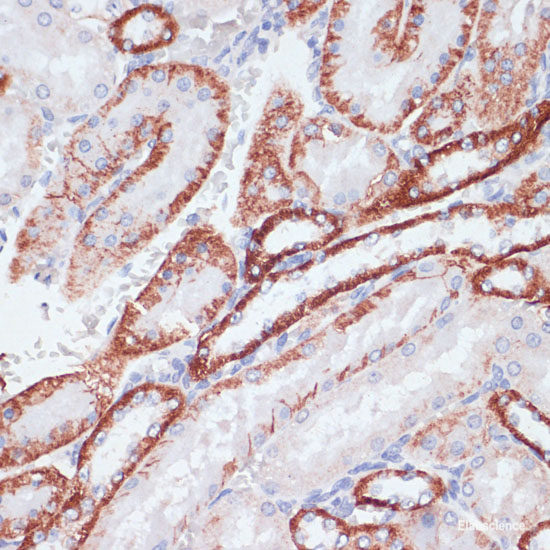

Product information "Anti-CD71"

This gene encodes a cell surface receptor necessary for cellular iron uptake by the process of receptor-mediated endocytosis. This receptor is required for erythropoiesis and neurologic development. Multiple alternatively spliced variants have been identified. Protein function: Cellular uptake of iron occurs via receptor-mediated endocytosis of ligand-occupied transferrin receptor into specialized endosomes. Endosomal acidification leads to iron release. The apotransferrin-receptor complex is then recycled to the cell surface with a return to neutral pH and the concomitant loss of affinity of apotransferrin for its receptor. Transferrin receptor is necessary for development of erythrocytes and the nervous system. A second ligand, the heditary hemochromatosis protein HFE, competes for binding with transferrin for an overlapping C-terminal binding site. Positively regulates T and B cell proliferation through iron uptake (PubMed:26642240). [The UniProt Consortium]

| Keywords: | Anti-TFRC, CD71 Polyclonal Antibody |

| Supplier: | Elabscience |

| Supplier-Nr: | E-AB-61161 |

| Application: | WB |

| Antibody Type: | Polyclonal |

| Conjugate: | No |

| Host: | Rabbit |

| Species reactivity: | human, mouse, rat |

| Immunogen: | Recombinant protein of human TFRC |